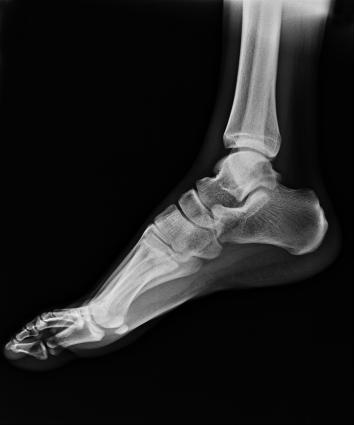

多功能動態(tài)平板DR,采用U型臂結構,具有靜態(tài)DR攝影、數(shù)字透視、數(shù)字造影和可視化攝影的功能。

滿足不同身高的受檢者快速地進行胸片的靜態(tài)及動態(tài)檢查,適合大規(guī)模體檢。